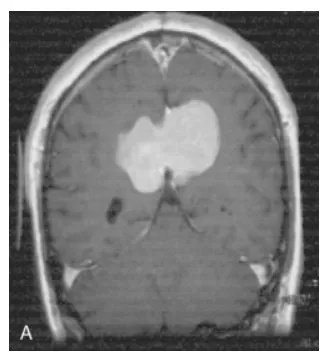

一名48岁的男性患者面临着一个严峻挑战:他的脑膜瘤不仅位置险要——紧贴直窦这一大脑核心静脉结构(A),这不仅让手术难以彻底切除,更意味着未来复发的风险极高。

30年前,在当时神经外科技术尚不发达的年代,这场手术无疑是一次“冒险”。然而,在医生精湛的操作下,在保护重要神经功能的前提下尽可能切除肿瘤(B)。针对少量残留病灶,又进行了辅助放疗。令人惊喜的是,在接下来超过13年的随访中,影像检查一次次带来好消息:肿瘤没有复发(C)。